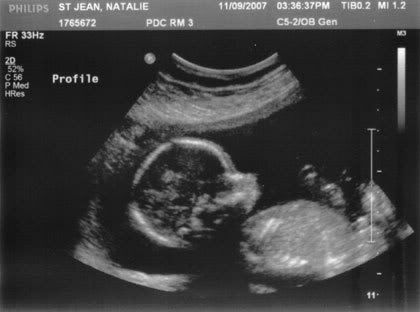

Our kiddo was NOT at all shy…

I think we both teared up when she said boy. I just knew from the start…. so it looks like mother’s intuition was right in this case! His name is/will be Devin Alin!

His sweet little face

The first glance was the baby curled up in a ball, which made me worry, but he didn’t stay there for long. For the first 10 minutes or so she was measuring the baby’s head, arms, heart, etc, in addition to checking on the position of my placenta and how my cervix was doing. I was trying to enjoy it, but at the same time I really wanted her to hurry up and get down to the important part. lol We kept seeing the baby’s hand all outstretched, all five little fingers. Looks like long little fingers, just like mama. :mushy: It was hard to get my bearings straight, as she was moving the U/S wand around so much to get the best angle for pictures. Baby was definitely constantly moving though… she was kind of talking to him, “Come on baby, move a little…” She’d wiggle the wand around a little as if trying to convince him to move around.